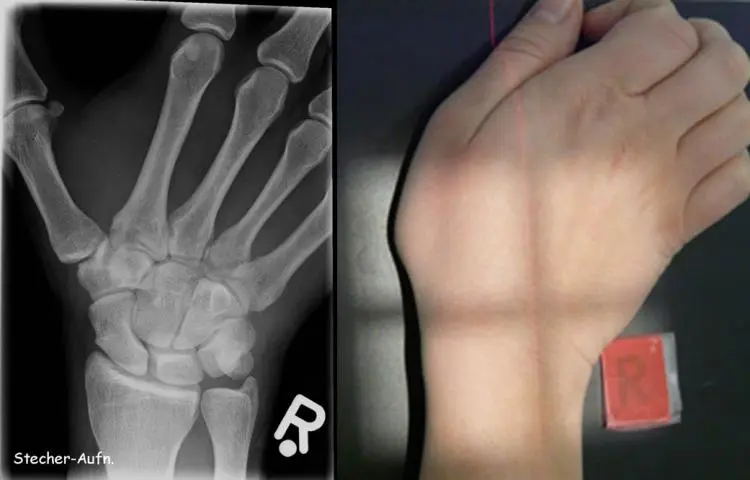

- Hand- oder Fingerbruch: Schmerz in der Hand oder den Fingern, Schwellung oder Bluterguss in der Hand oder den Fingern, Schwierigkeiten beim Bewegen der Hand oder der Finger.

Diagnose eines Bruchs

Wenn Sie vermuten, dass Sie einen Bruch haben, ist es wichtig, sofort einen Arzt aufzusuchen. Der Arzt wird Ihre Krankengeschichte erfragen, eine körperliche Untersuchung durchführen und möglicherweise bildgebende Verfahren anordnen, um die Diagnose zu bestätigen.

Die folgenden bildgebenden Verfahren werden häufig verwendet, um Brüche zu diagnostizieren:

- Röntgenaufnahme: Röntgenaufnahmen sind die am häufigsten verwendeten bildgebenden Verfahren zur Diagnose von Brüchen. Sie zeigen die Knochenstruktur und können einen Bruch klar sichtbar machen.